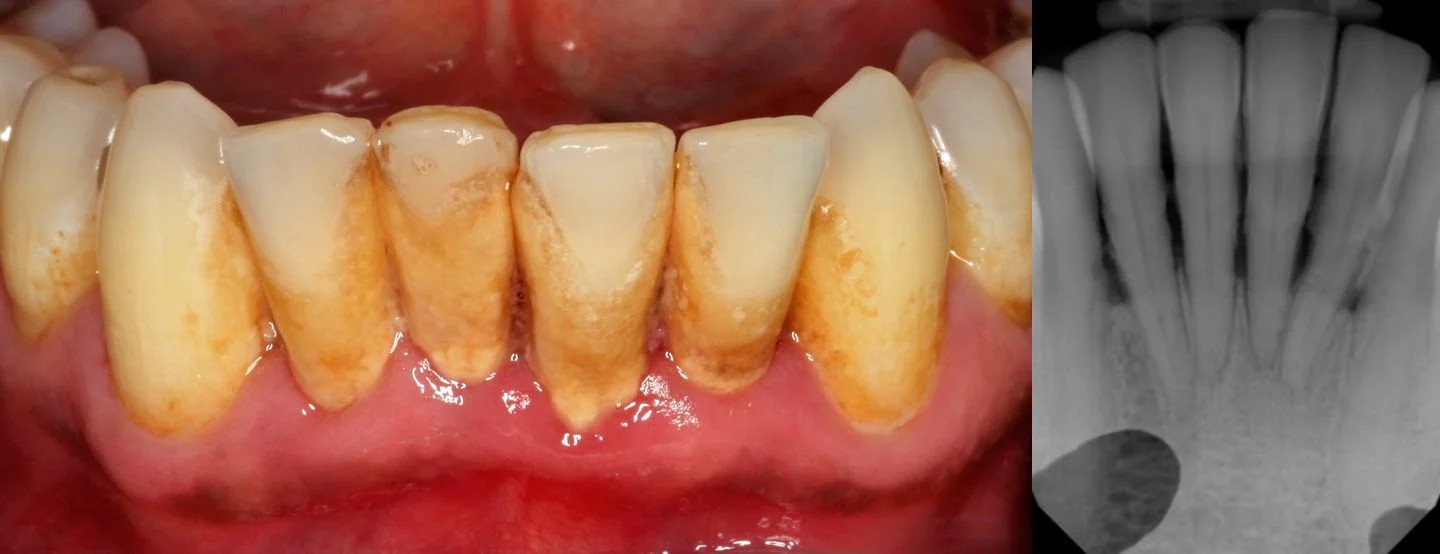

Cleaning at this point usually means deep scaling in order to remove plaque and calculus build-up from the roots of the teeth as well as on the surface of them. Getting Diagnosed With Periodontal Disease. Instead you will require special ongoing gum and bone care procedures known as Periodontal Maintenance Therapy to keep the disease under control and keep your mouth healthy.

Scaling is when your dentist removes all the plaque and tartar hardened plaque above and below the gumline making sure to clean all the way down to the bottom of the pocket. Deep cleaning is typically recommended for individuals that have gingivitis a mild form of gum disease or to address periodontal disease which is a more serious gum infection where inflammation or infection of the gums and surrounding oral tissues occurs. Severe cases sometimes involve surgical procedures where diseased gum tissue is removed and grafts are used to replace them. Patients who do not follow proper dental care routines are especially prone to a condition called periodontal disease or gum disease. Deep Cleaning 1. Signs that you might need a deep cleaning include bleeding gums receding gums and loose teeth. Typically dentists advise deep cleaning when the depth of the space between your gums and teeth exceeds.

Signs that you might need a deep cleaning include bleeding gums receding gums and loose teeth. Scaling and Root Planing This deep cleaning has two parts. Although a deep cleaning also.